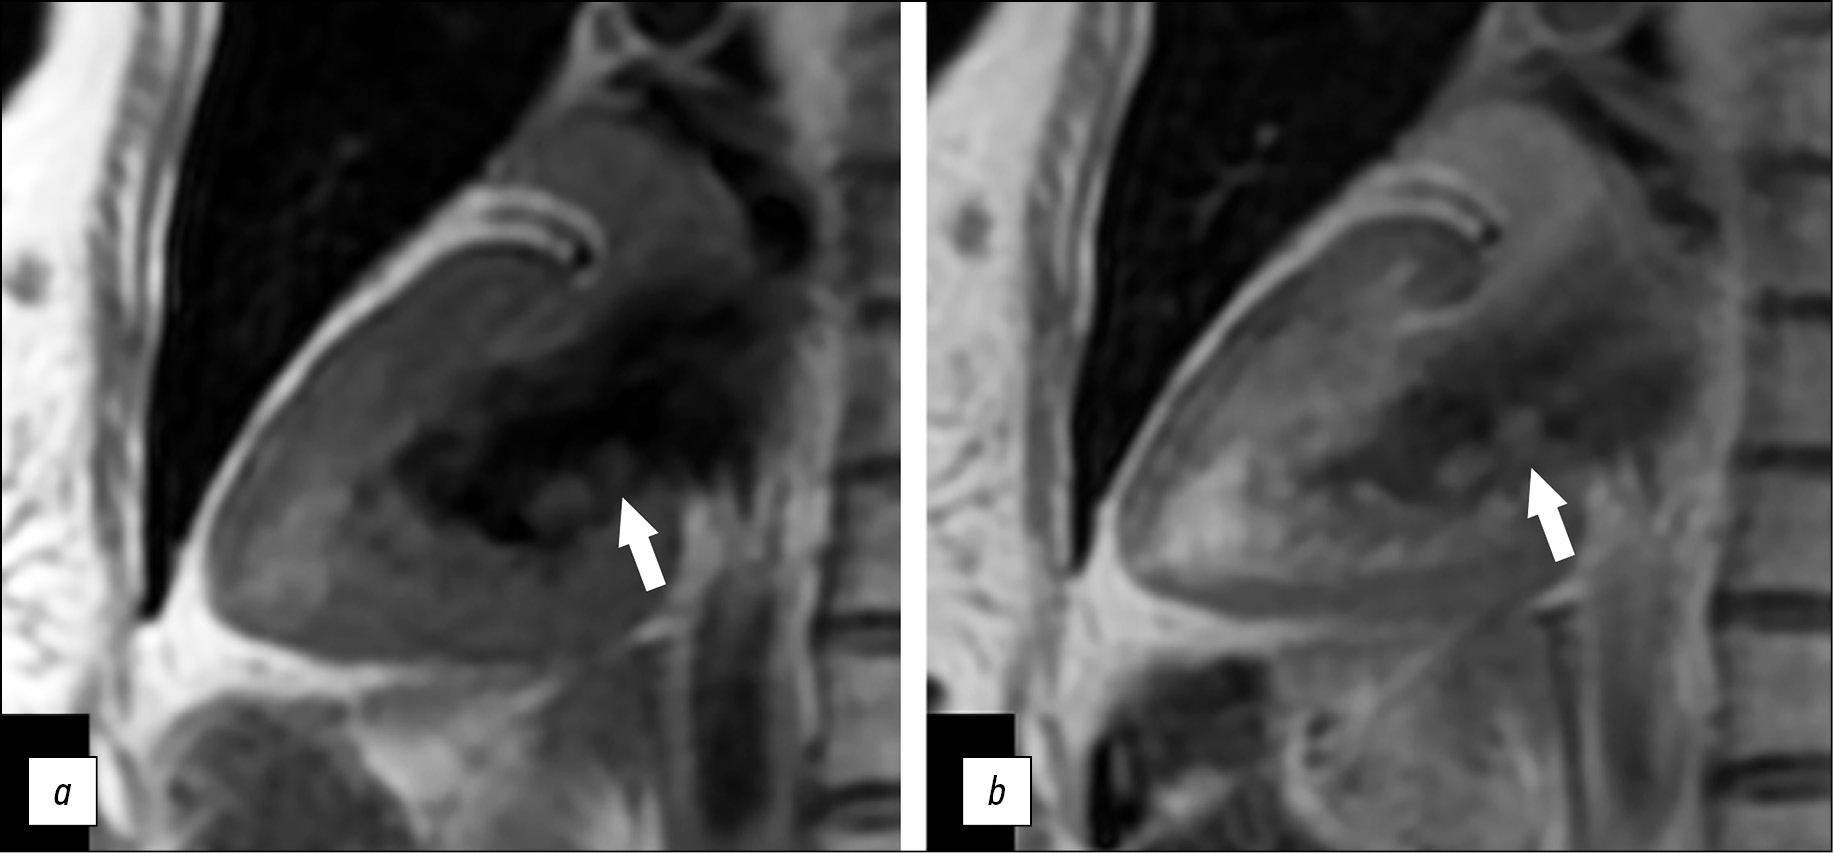

A series of Fiesta-CINE functional examinations in standard axes (two- and four-chamber long axis with 8 mm slice thickness and 0 mm inter-slice interval) was performed after a series of panoramic and axial chest scans in cardiac MRI. Tumor visualization in standard cardiac MRI views was difficult because of the small size of the mass. Optimal mass visualization was obtained in the modified Fiesta-CINE two- and four-chamber views (Fig. 2).

Fig. 2. Magnetic resonance imaging of the heart, two-chamber view: a, left ventricular systolic phase; b, left ventricular diastolic phase. Additional mass on the posterior mitral valve leaflet (black arrows).

A small round-shaped mass (5 × 8 mm in size) on the posterior mitral valve leaflet on the left atrial side was confirmed. The examination was performed before and after early and delayed contrast enhancement using T2 SS, FSE, and FS pulse sequences—T2 WI with signal suppression from blood and adipose tissue—and PS MDE (PSIR), TI 250 ms postcontrast images to obtain tissue mass characteristics. A contrast agent (gadopentetic acid) was injected at 0.2 ml/ kg body weight.

After delayed contrast enhancement, an increased signal was observed compared to the native T1-WI series (Fig. 3).